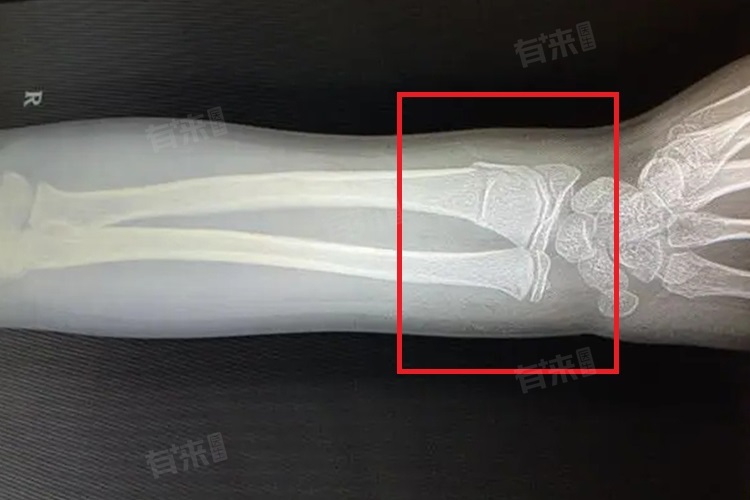

- 较为严重的骨折,比如粉碎性骨折,骨折部位的骨头碎成多块,对骨骼的重建带来很大困难。即使通过手术将碎骨块复位并固定,由于骨骼结构被严重破坏,愈合后的手臂可能无法完全恢复到受伤前的状态。在愈合过程中,可能会出现骨骼愈合不良,如骨痂生长不均匀,导致手臂的力量、活动范围或者灵活性受到影响。

手臂骨折的治疗需综合多方面因素,对简单骨折,可采用石膏或夹板固定等保守治疗,保持骨折部位稳定促进愈合,严重骨折如粉碎性骨折多需手术复位固定。术后要重视康复训练,避免肌肉萎缩和关节僵硬,注意预防感染等并发症。